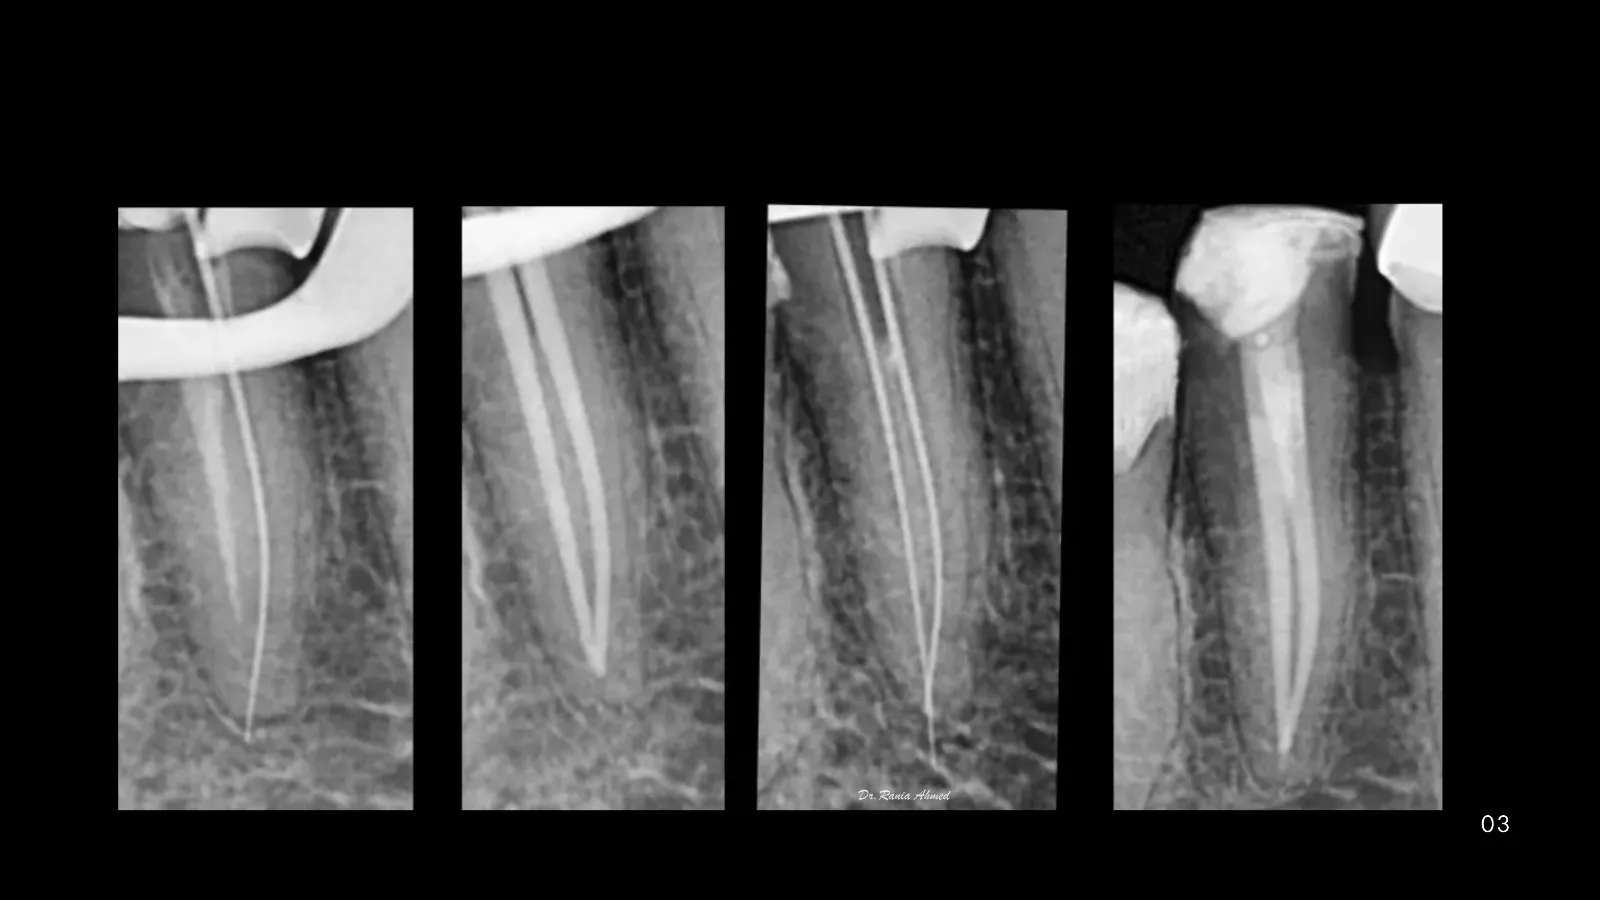

Endodontic Treatment